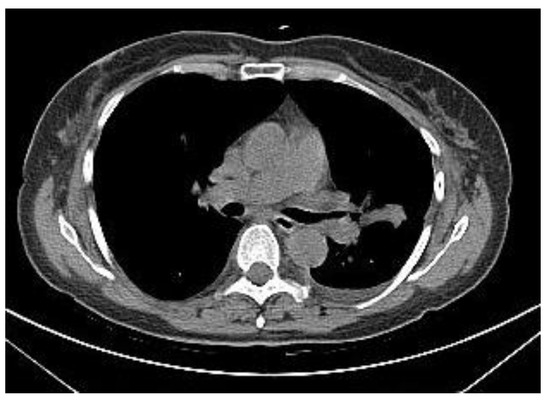

2.2.1. TIME 0: Lesion marking and SPECT Analysis